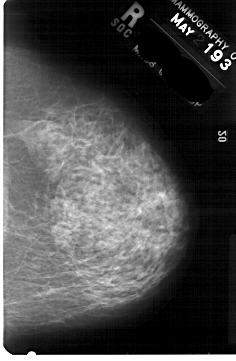

A_1834_1.LEFT_MLO

LEFT_MLO LINES 5491 PIXELS_PER_LINE 4111 BITS_PER_PIXEL 12 RESOLUTION 43.5 OVERLAY

FILE: A_1834_1.LEFT_MLO.OVERLAY

TOTAL_ABNORMALITIES 1

ABNORMALITY 1

LESION_TYPE MASS SHAPE LOBULATED MARGINS OBSCURED

ASSESSMENT 4

SUBTLETY 4

PATHOLOGY BENIGN

TOTAL_OUTLINES 1

BOUNDARY